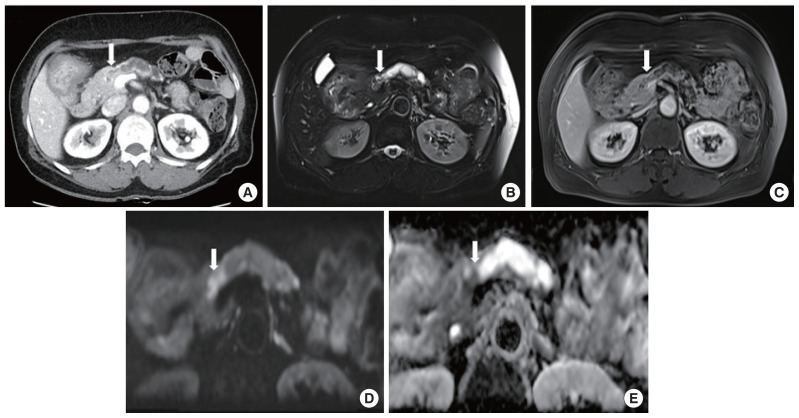

胰腺远端切除加脾切除术被认为是治疗胰腺尾癌和胰体癌的标准手术。不过,良性或低度恶性肿瘤(包括粘液性囊腺瘤和导管内乳头状粘液瘤)可选择脾切除术。如果进行了边界病变的保脾胰腺远端切除术(SPDP),术后病理结果确诊为胰腺癌,如果是 R0 切除术,是否有必要进行额外的脾切除术仍值得商榷。作者希望报告两例在 SPDP 术后病理诊断为胰腺癌的临床病例,在观察期间没有进行额外的脾切除术。

Distal pancreatectomy with splenectomy is considered the standard operation for pancreas tail and body cancer. However, splenectomy may be option for benign or low-grade malignant tumors including mucinous cystadenoma and intraductal papillary mucinous neoplasm. If spleen-preserving distal pancreatectomy (SPDP) with borderline lesion is performed and pancreas cancer is diagnosed on postoperative pathologic finding, if it is R0 resection, the necessity of additional splenectomy remains questionable. The authors would like report two clinical cases diagnosed as pancreatic cancer on postoperative pathology after SPDP and under observation without additional splenectomy.